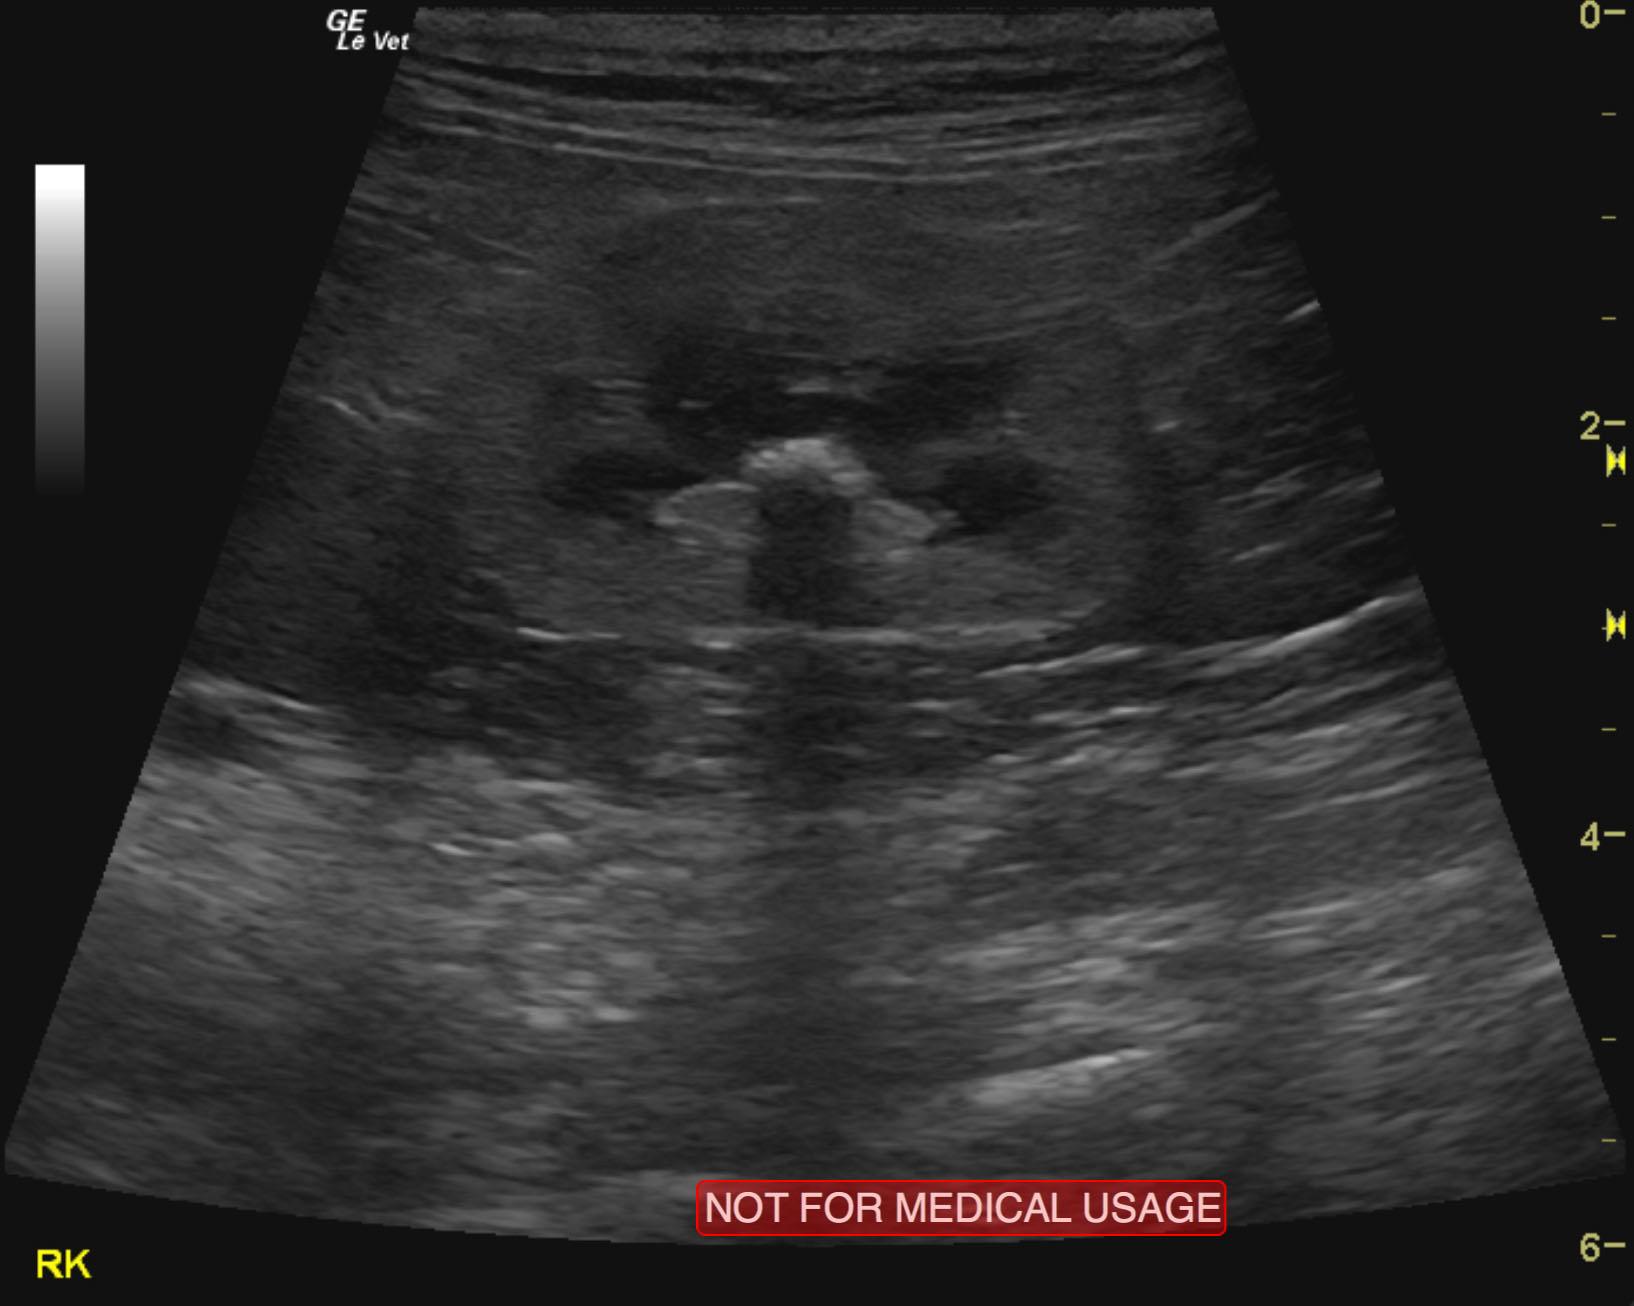

A 5-year-old male neutered DMH cat was presented for evaluation of PU/PD, abnormal behavior, and inappropriate urination (periuria). Low-normal specific gravity (1.014) was evident on urinalysis. CBC was within reference range, but serum biochemistry revealed azotemia.